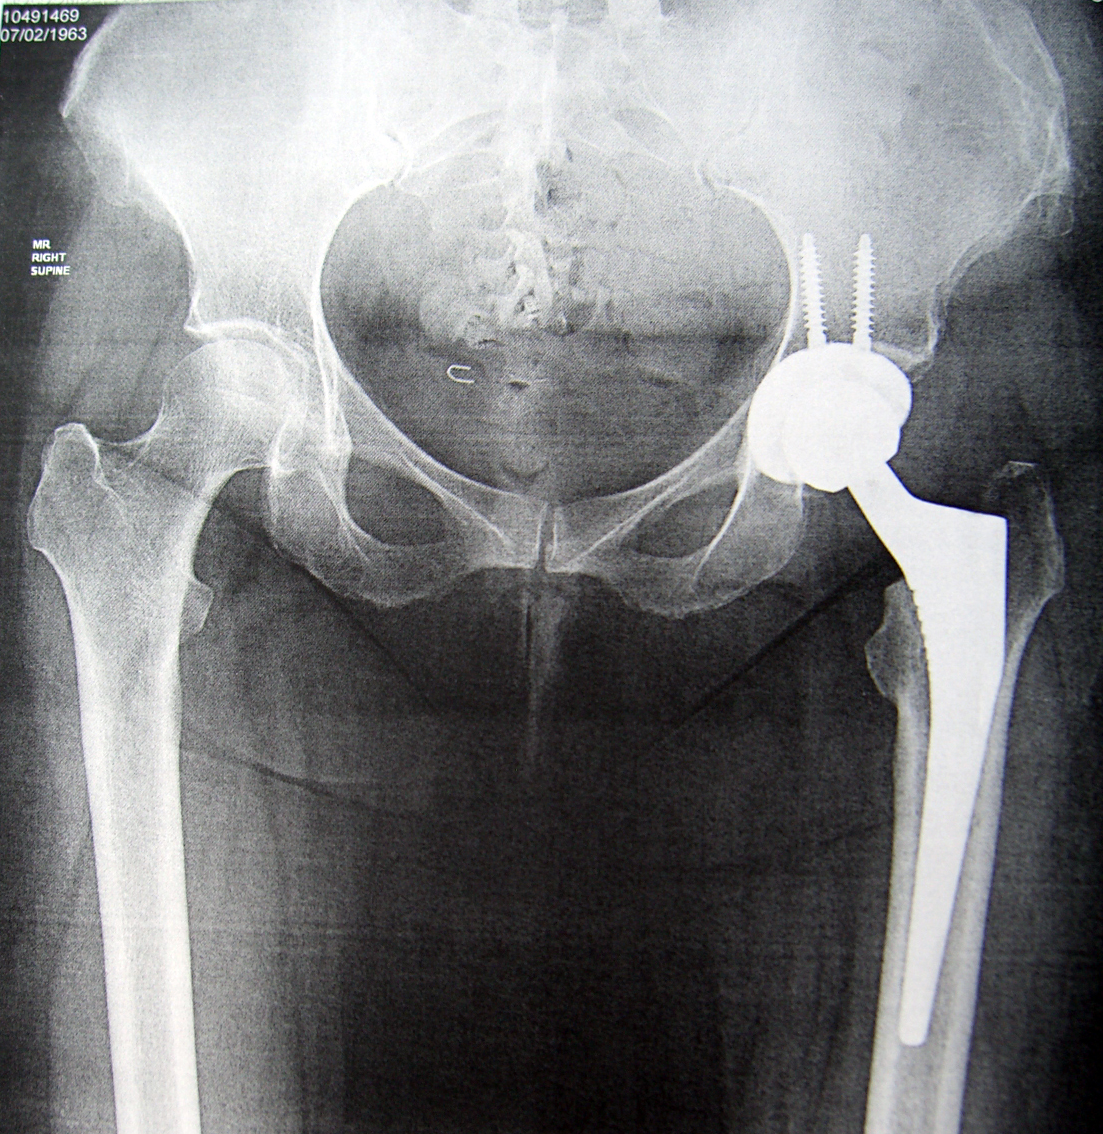

My New HIp. 14th April 2015  by Dr. Springer, OrthoCarolina

Another view of my New Hip - by Dr. Springer - OrthoCarolina

Another view of my New Hip – by Dr. Springer – OrthoCarolina